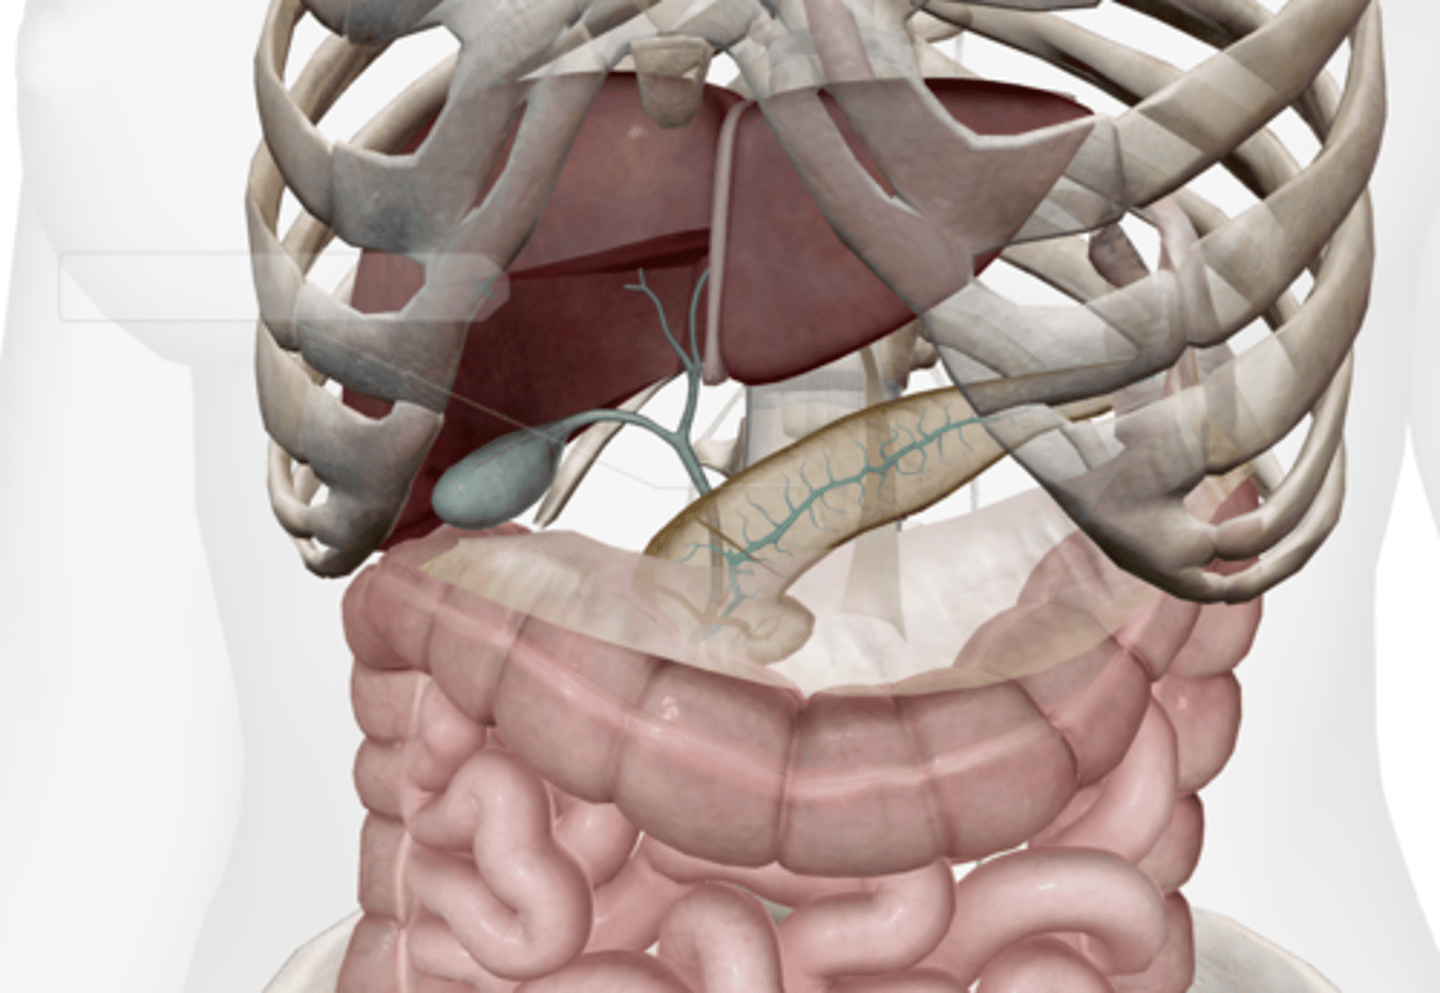

Gallbladder

Cystic duct

Common hepatic duct

Common bile duct

Pancreas

Main pancreatic duct (duct of Wirsung)

Accessory pancreatic duct (duct of Santorini)

Liver

Hepatic artery & vein

Falciform ligament

Duodenum

Duodenal papilla